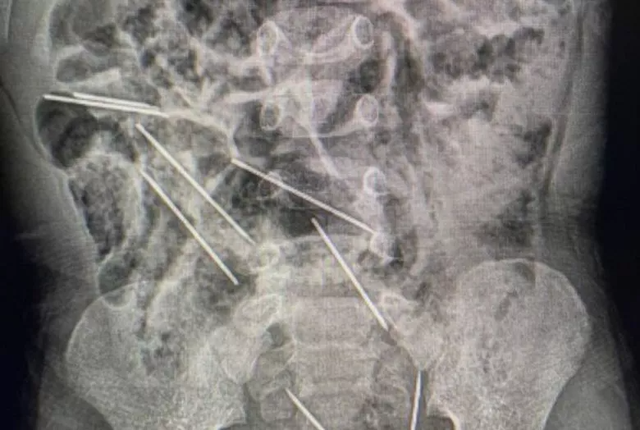

Setelah melakukan serangkaian pemeriksaan termasuk CT Scan, ahli bedah Efraín Salazar Tito langsung melakukan tindakan operasi bedah dan menemukan delapan jarum bersarang di seluruh perut anak tersebut.

“Dua (jarum) di peritoneum di sisi kanan, tiga di sisi kiri, satu di dinding perut, dan dua lainnya berada di antara kandung kemih dan rektum,” papar rilis dari San Martin Regional Government dilansir Newsweek.

Beruntung, 8 jarum yang ditelan bocah di Peru berhasil dikeluarkan lewat operasi bedah yang memakan waktu dua jam. Dokter juga berhasil mengobati lesi atau luka di usus kecil anak tersebut.